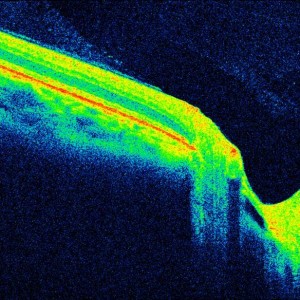

Grubenpapille (siehe Anmerkung)

Papillengrube (аббревиатура: Grube)